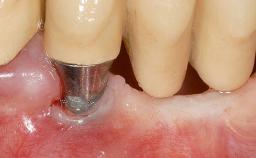

Implant Placement in the Esthetic Zone and Coverage of Multiple Gingival Recessions

This case illustrates use of a modified ‘tunnel’ technique, which has been shown to be highly effective in root coverage procedures. The tunnel technique is used to achieve soft-tissue augmentation across the anterior area, including the planned implant site, using collagen matrix as grafting material. The patient is a 47-year-old woman with high esthetic expectations. Her main concern was the appearance of the anterior teeth and their “elongation”.